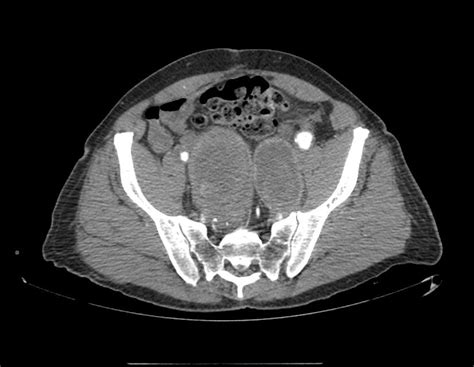

So, you’ve got some symptoms, or maybe you’re in a high-risk group and your doctor suggests a check-up. How do doctors actually find these internal iliac artery aneurysms? Well, thankfully, there are several effective diagnostic tools available. The first step is usually a physical examination . Your doctor might be able to feel a pulsating mass in your abdomen or pelvic area, especially if the aneurysm is large. They will also take a detailed medical history, asking about your symptoms, family history of aneurysms, and risk factors like smoking and high blood pressure. If there’s a suspicion of an aneurysm, imaging tests are the next crucial step. Ultrasound is often the initial imaging modality used. It’s non-invasive, readily available, and can provide a good view of the iliac arteries, helping to identify the presence, size, and location of an aneurysm. However, ultrasound can sometimes be limited by factors like obesity or bowel gas. For more detailed and definitive imaging, doctors often turn to Computed Tomography (CT) scans or Magnetic Resonance Angiography (MRA) . A CT scan, especially a CT angiography (CTA), uses X-rays to create detailed cross-sectional images of your body. CTA involves injecting a contrast dye into your bloodstream, which highlights the blood vessels, allowing for very precise visualization of the aneurysm, its dimensions, and its relationship to surrounding structures. MRA uses magnetic fields and radio waves to create detailed images of blood vessels, and it’s another excellent option, particularly for patients who may need to avoid radiation or contrast dye. Sometimes, a traditional angiogram might be performed. This is a more invasive procedure where a thin, flexible tube (catheter) is inserted into an artery (usually in the groin) and guided to the iliac artery. Contrast dye is injected directly into the artery, and X-ray images are taken. While it’s more invasive, it can provide very detailed information about the blood vessels and is often used when planning for treatment. The choice of imaging test often depends on factors like the availability of the technology, the patient’s overall health, and the specific information the doctor needs. The goal of these diagnostic tests is not just to confirm the presence of an aneurysm but also to accurately measure its size, assess its shape, and determine its exact location. This information is critical for deciding on the best course of action, whether that’s watchful waiting or immediate intervention. So, rest assured, if an internal iliac artery aneurysm is suspected, doctors have a robust arsenal of tools to detect it accurately. Remember, early detection is key to successful management and preventing serious complications, so don’t hesitate to discuss any concerns with your healthcare provider, guys. It’s all about getting the right information to make informed decisions about your health.